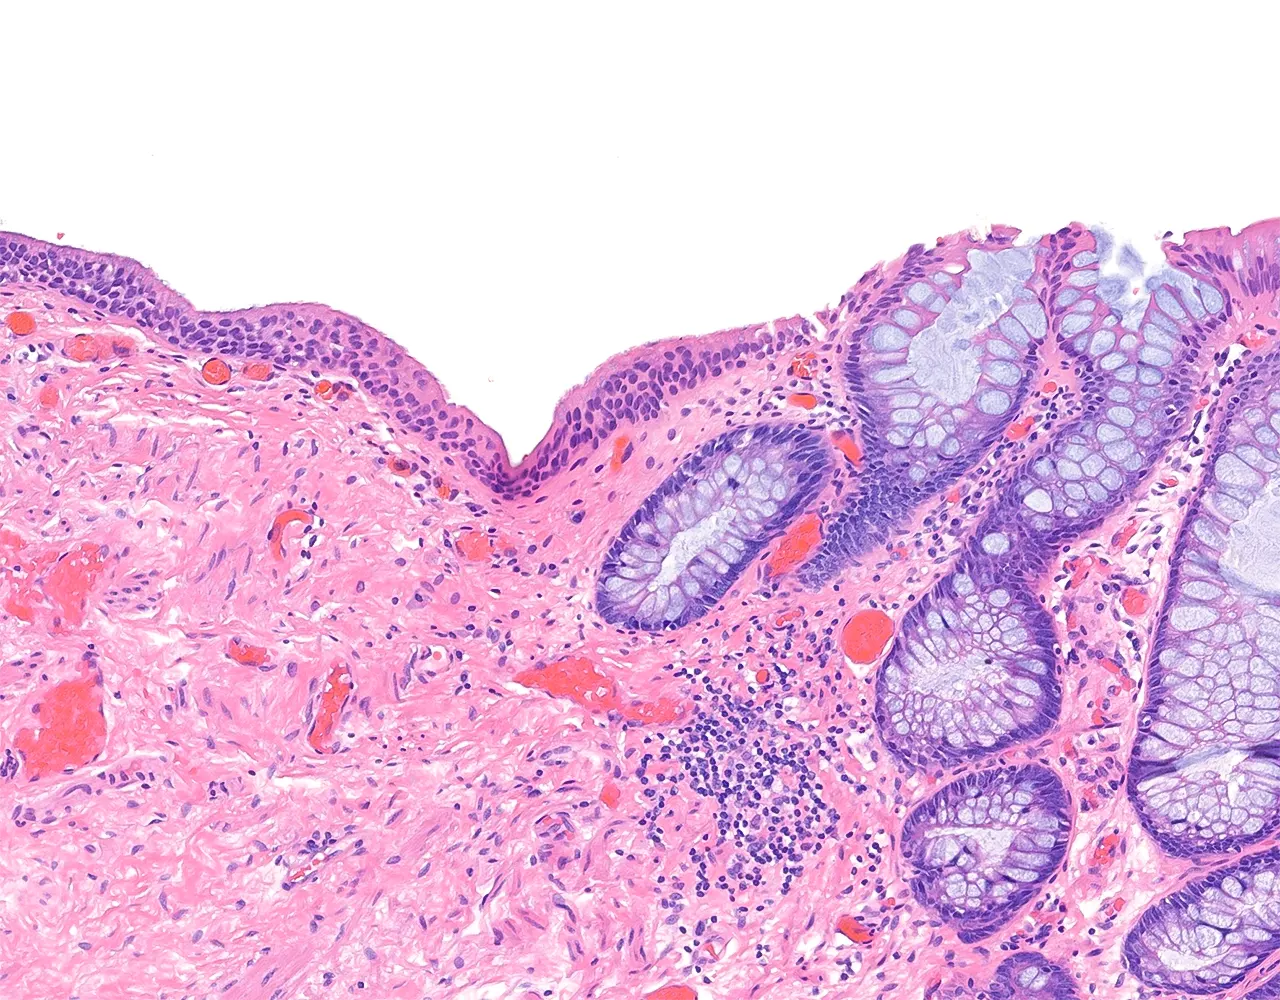

- Le gros intestin est responsable de l’absorption de l’eau et des électrolytes, de la sécrétion de mucus pour la lubrification, de la compaction et du stockage des matières fécales, ainsi que de la contribution aux interactions entre l’hôte et le microbiote.

- L’appendice est un diverticule borgne naissant du caecum.

- Il contribue principalement à la fonction immunitaire locale grâce à son abondant tissu lymphoïde et peut également agir comme réservoir du microbiote intestinal normal.